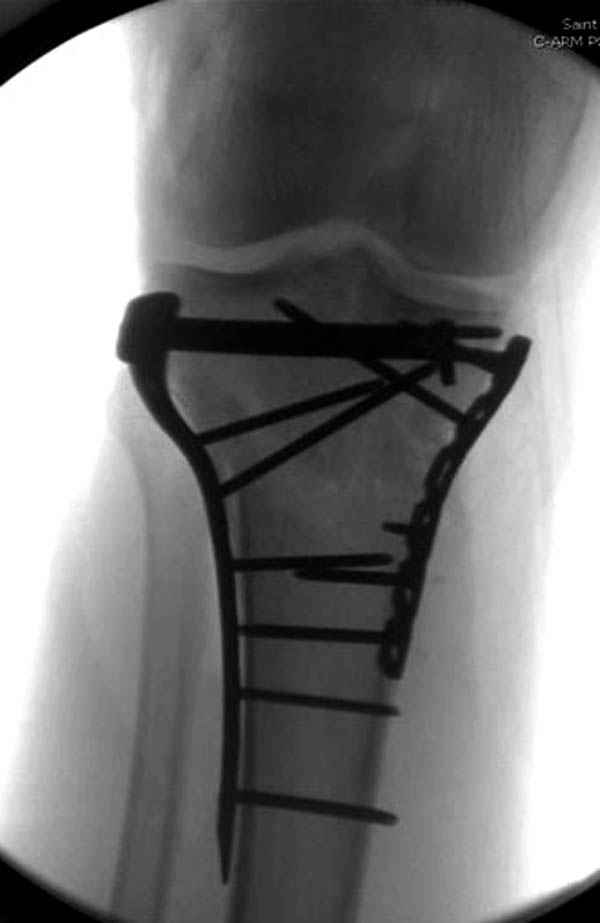

Надеюсь, представленные снимки разных случаев помогут разобраться в тактике, и критика примется без личной обиды.

Вложение не в текстовом формате было извлечено…

Имя     : 14 Med plateau fx.JPG

Тип     : image/jpeg